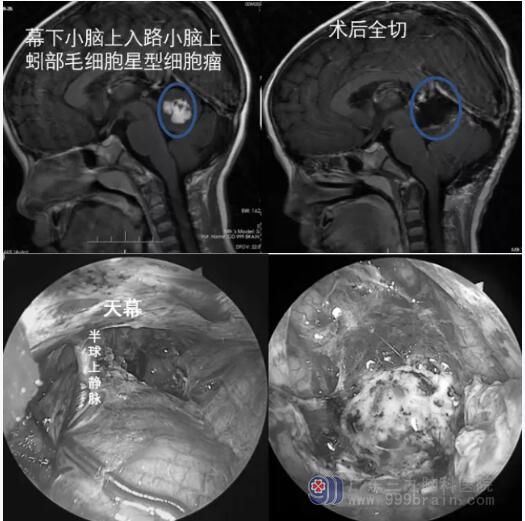

内镜在开颅手术中的应用

神经内镜辅助开颅手术可用于治疗前、中、后颅窝病变。眶上和小翼点内镜辅助锁孔入路已成功地治疗位于前颅窝、第三脑室前部肿瘤和夹闭前循环动脉瘤;神经内镜下经乙状窦后入路实施小骨窗切除术已广泛应用于微血管减压术;神经内镜下经幕下小脑上入路已广泛应用于松果体区肿瘤的切除。